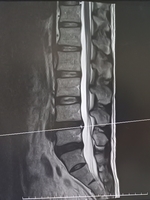

身体の痛みやしびれ、不調はお任せ下さい。まずは、お電話下さい。